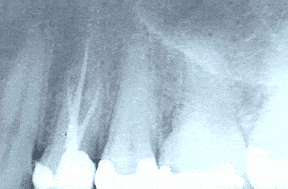

Once you are fully at ease, our dentists carefully remove any existing fillings to access the core of the tooth using high-precision instruments. Throughout the procedure, we rely on advanced imaging tools, including digital X-rays and intraoral cameras, to guide our work and maintain exact accuracy while protecting the healthy structure of your tooth.